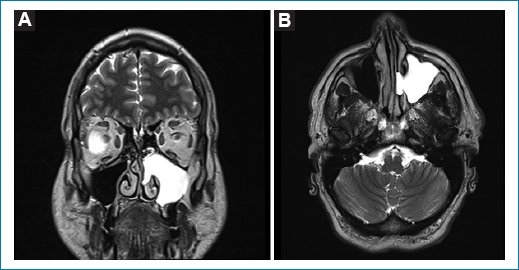

Se le realizó una RM que mostró una lesión hiperintensa que ocupaba la totalidad del seno maxilar izquierdo, con extensión hacia la cavidad nasal sin erosión ósea (Fig. 1).

Figura 1. Resonancia magnética. A: corte coronal, secuencia T2, que muestra una lesión hiperintensa que ocupa la totalidad del seno maxilar izquierdo, con extensión hacia la cavidad nasal sin erosión ósea. B: corte axial, secuencia T2, que muestra una lesión hiperintensa que ocupa la totalidad del seno maxilar izquierdo, con extension hacia la cavidad nasal sin erosión ósea.